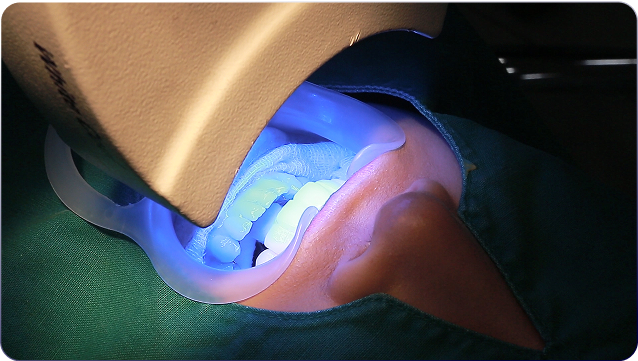

하얀 치아까지 챙기세요.

AI 검진· 치아미백 · 프리미엄

02 치아미백 첫 달 2회 제공 22만원 VAT 포함

치아미백 무제한